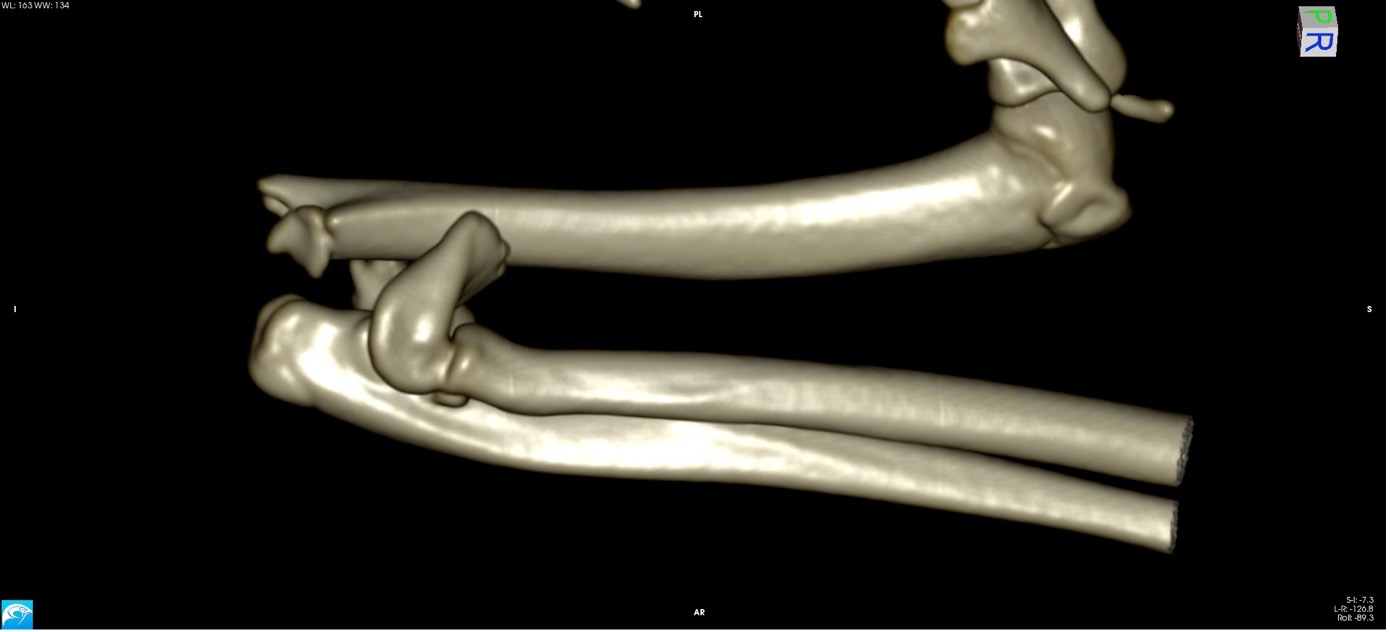

Exemple 3 :

Figure 9 : Pré-Op

L’avènement récent des plaques anatomiques constitue une nouvelle option dans le traitement de ces fractures : dans l’exemple 3 (chat Ragdoll), une plaque anatomique médiale de 2 mm acceptant des vis de 1,6 et 2 mm a été utilisée seule avec succès.